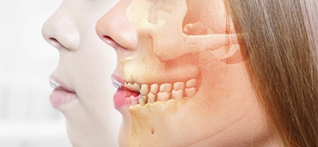

与鼻根部或颌部相比,唇部过分向前突出的容貌特征被称为外突嘴。唇部过分向前突出会给人一种生硬倔强、稚气未脱的印象。外突嘴分为上下门齿向前突出和上下门齿以及上下颌骨一同向前突出的情况。大部分的韩国人除了上下门齿向前突出外,还伴有上下颌骨向前突出的情况。